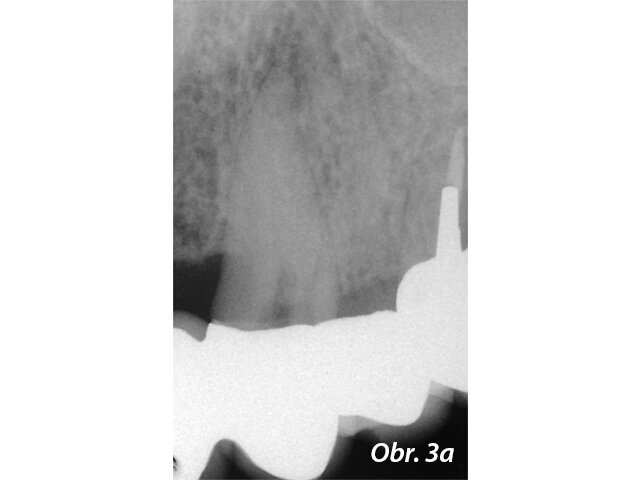

Kořenové perforace

Perforace v dřeňové dutině nebo kořenovém kanálku významně mění prognózu zubu. Oprava perforace pomocí biokompatibilního těsnicího materiálu jako je MTA může ohrožené zuby ušetřit (Mente a spol. 2014) (obr. 3a–e).

Endodonticky ošetřený zub s píštělí

Po reendodoncii se ukázal otevřený apex

Aplikace PD MTA White s MAP systémem

Kondenzace MTA papírovým čepem

Postoperační RTG ukazuje výplň MTA a rekonstrukci se světlovodným čepem